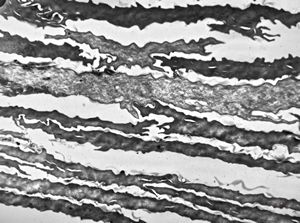

F, 39y. | collagenous and elastin fibers from corium

F,68y. | collagenous and elastin fibers from corium